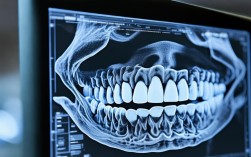

拍牙齿CT(通常指锥形束CT,简称CBCT)是牙齿矫正(正畸)过程中非常重要且常见的检查手段,它能为正畸医生提供传统牙片(如全景片、头颅侧位片)无法比拟的三维立体信息,对于制定精准、安全的矫正方案至关重要,以下是关于矫正牙齿拍CT的详细说明...